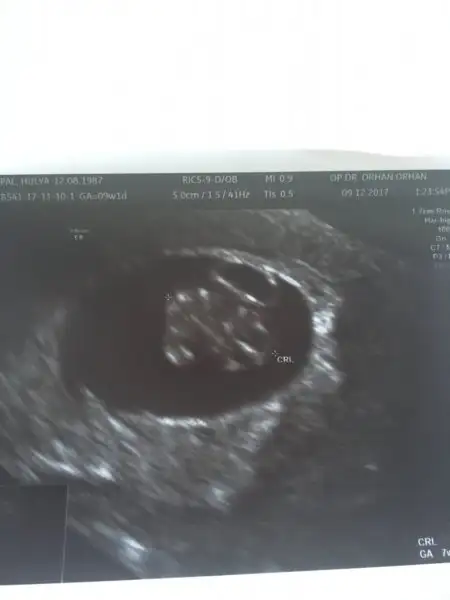

Bana da tahminde bulunabilir misiniz acaba ? 7 haftalık burda karından çekildiUSG karındansa erkek gibi, vajinalsa kız gibi

bebegin7-8 haftalıkkenki usg resimine direkt baktıgınızda;

bebek kesenin soluna yakınsa bebek erkek,

sagına yakınsa kız.